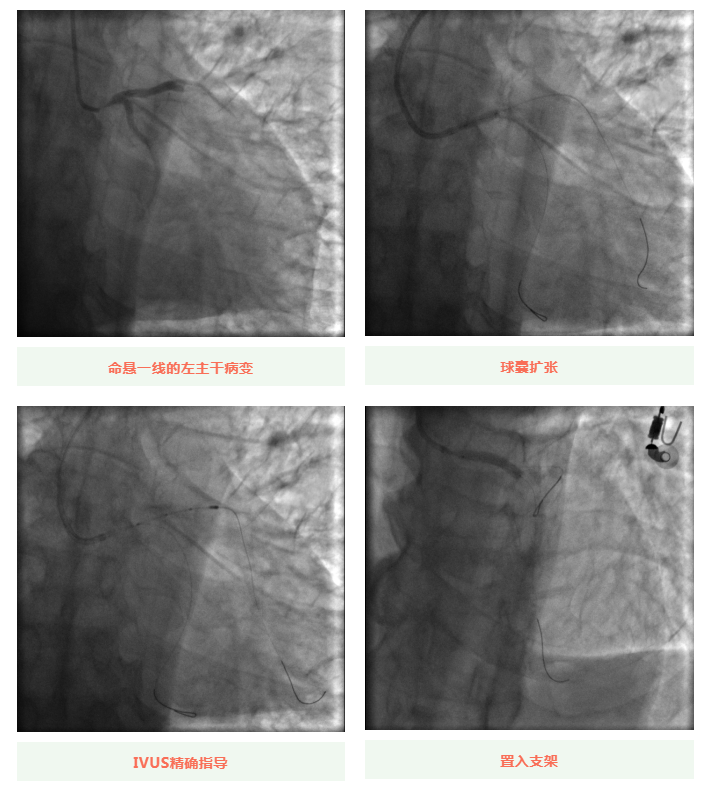

心血管内科副主任徐先进在主任助理农彦林和主任汪念东的配合下行冠状动脉造影,结果如术前判断一致,左主干重度狭窄,患者命悬一线。对团队紧急处置非常信任的李阿姨,毫无疑虑地听取了术者的建议,同意在血管内超声(IVUS)的精准指导下,在患者左主干内植入一枚支架,成功拯救了患者的生命。